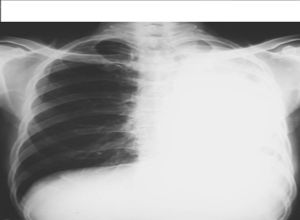

一葉或一段肺組織過度膨脹,壓迫正常肺組織、縱隔器官及心血管系統,是造成嬰幼兒急性呼吸窘迫的常見病因之一。僅見於新生兒或幼兒,1/3病例出生後即刻發病,50%發生在出生後1個月,僅5%在出生後6個月發病,男多於女,常見於雙肺上葉(以左上肺葉最多見),其次為右肺中葉,下葉少見。

臨床表現為單葉或單側肺透明膜病。理論上肺實質自身異常是此病的可能病因,但未被證實,有人研究切除後肺葉的形態學,可見肺泡數量增加,超過正常50%,並且肺泡大小正常或增大,氣管及血管的數量和結構正常,提示:此病為肺囊泡巨大症或出生後肺泡異常增加。